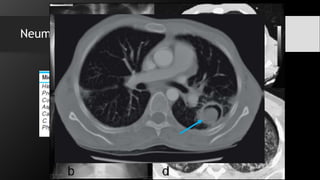

Neumatocele:

Es una dilatación del espacio aéreo como

consecuencia de obstrucción bronquial por

proceso infeccioso, sus paredes por lo

general son finas pero suele estar rodeado

de infiltrados alveolares

Neumatocele: Es una dilatacióndel espacio aéreo como consecuencia de obstrucción bronquial por proceso infeccioso, sus paredes por lo general son finas pero suele estar rodeado de infiltrados alveolares